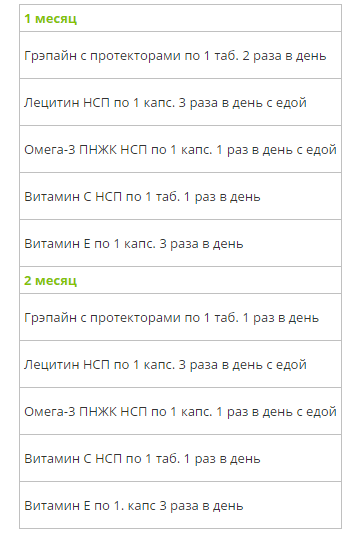

Предлагаем две схемы приема данного набора:

— Если Вы уже испытываете проблемы со здоровьем, связанные с плохим состоянием сосудов и нарушением микроциркуляции, рекомендуем Вам интенсивный 2х месячный курс.